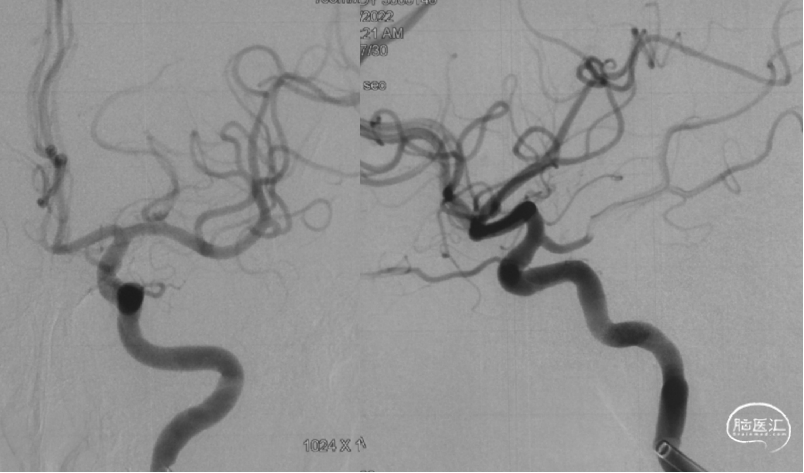

在NeuronMAX支撑下,微导丝/微导管辅助4MAX抽吸导管到位,进行抽吸。

抽吸一次,达到eTICI 2C再通。

● 本例患者采用的是抽吸取栓。与支架取栓相比,在器械成功到位的情况下,可能能够减少血管移位牵拉带来的出血风险。这例患者大脑中M2闭塞近端血管直径测量约1.6mm,4MAX导管远端外径4.3F(1.42mm),内径0.041''(1.04mm),能够实现远端到达和抽吸目的。